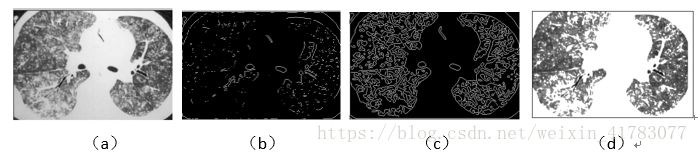

遗传算法擅长于全局搜索, 但局部搜索能力不足, 所以常把把遗传算法和其它算法结合起来应用。如Guan,X.-W.等人[12]在2011年提出一种遗传算法,用全局搜索能力和类间最大变化作为适应度函数,算法结合形态学理论提取图像边缘,实现分割,分割结果如图6所示。实验结果表明,这种遗传算法性能稳定,融合结果理想;Jaffar,M.A.等人[13]在2009年提出一种结合支持向量机的遗传算法,在肺部CT图像中对肺结节进行检测,分割效果理想;Liu,J.等人[14]提出了一种遗传神经网络算法来分割皮肤癌图像,执行基于遗传算法的神经网络的权重和阈值优化来改进BP神经网络的收敛速度,由该方法分割的皮肤癌图像可得到连续的边缘和清晰的轮廓,可以用于皮肤癌的定量分析和鉴定。

图6 遗传算法分割医学图像。(a)原始图像(b)提取边缘的图像(c)边缘图像曲线拟合结果(d)分割后的图像